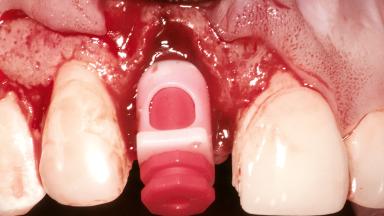

Replacement of a Maxillary Right Central Incisor Using an Early Loading Protocol

A healthy 26-year-old woman was referred for evaluation and treatment of her failing maxillary right central incisor (tooth 11). She reportedly traumatized the tooth at about age 9 and subsequently had repeated conventional and surgical endodontic procedures and fixed restorations. Despite these procedures, she had recurrent fistulas in the apical mucosa and a mid-facial pocket of 7 mm with suppuration. All other sites on the tooth probed 3 mm without inflammation. She presented with a medium biotype with triangularlyshaped teeth and a moderately high smile line, showing all of her papillas and a few millimeters of marginal gingiva in a full smile.Ceramic veneers were present on teeth 12, 21, and 22, and they were known to be somewhat bulky, eventually requiring replacement. She had a strong desire to avoid additional tooth preparation and would not consider a fixed dental prosthesis to replace tooth 11.

Bone Augmentation Horizontal|Simultaneous

Augmentation Materials Autogenous chips|Membrane

Soft Tissue Grafting Simultaneous